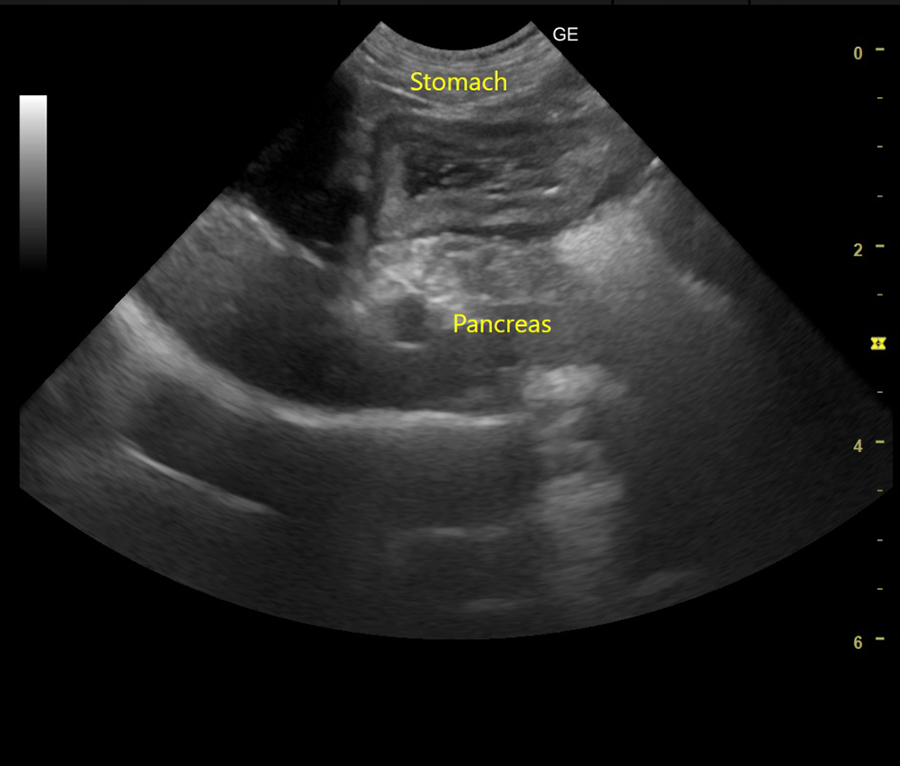

• 超音波検査

膵炎の診断には血液検査や超音波検査などが重要な役割を果たします。

当院では膵炎を疑う症状を認めた場合は、これらの検査を実施し、膵臓や周囲の臓器の状態を詳しく評価します。

超音波検査や内視鏡検査を組み合わせ、細胞や組織を採取することで消化器型リンパ腫の診断が可能です。